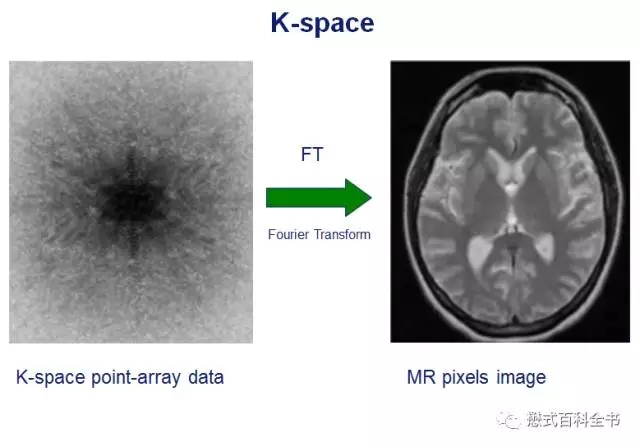

而磁共振图像则是通过反傅里叶变换(IFT),MR扫描的数据填充到K空间,利用K空间进行IFT得到磁共振图像。

磁共振成像,采集的数据,为了空间定位,需要用到几个方向的的梯度对空间进行编码,我们采集得到的数据并不是时间域函数,而是频率域函数。所以,我们需要对K空间中的数据进行IFT,得到时间域函数,并且解析出每个质子的空间定位,得到磁共振图像。

讲了这么多,大家只需要简单的记住,K空间就是储存磁共振原始数据的空间,可以通过K空间的原始数据进行非常复杂的数据后处理,得到磁共振图像。

图3:上图是一个K-space的示意图

上图是一个K空间的示意图,我们知道磁共振需要需要对质子进行空间定位,会用到不同方向的梯度磁场。